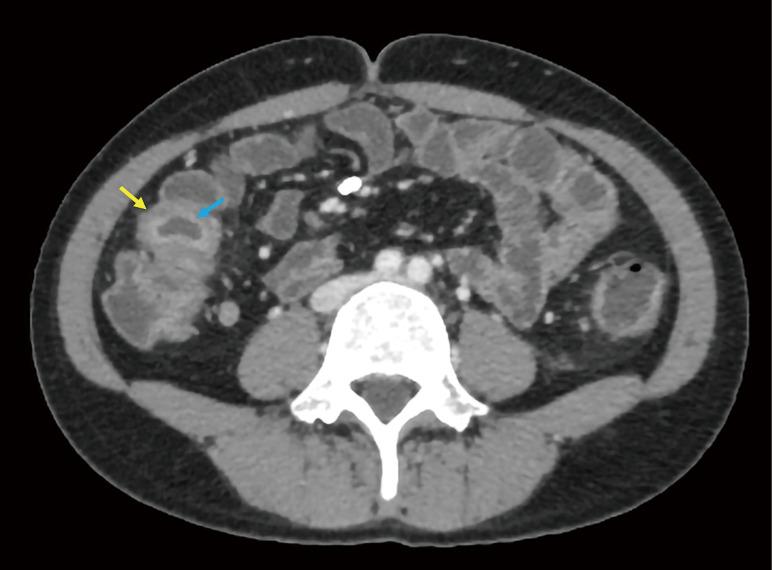

Creeping fat (CF), a characteristic structure of Crohn's disease (CD), is closely associated with surgery and prognosis but lacks a unified imaging assessment standard, and endoscopic and serological indicators have limitations in evaluating extra-intestinal lesions. The study aimed to explore the correlation between computed tomography (CT) value distribution changes of mesenteric-surrounding fat in CD and disease activity.

In this study, we retrospectively analyzed CT enterography (CTE) images from 47 pathologically confirmed CD patients and 25 randomly selected controls with suspected inflammatory bowel disease (IBD). Quantitative measurements were obtained for mesenteric adipose tissue density (mean of CT values) along key anatomical landmarks including the mesenteric root, superior mesenteric artery, inferior mesenteric artery, perilesional regions, intestinal stricture, and adjacent branching vascular spaces. Other evaluated parameters included bowel wall thickness, CT attenuation, enhancement patterns, and CF grading. Qualitative evaluations were made by comparing with endoscopic, serological, and histopathological results and simplified CD activity index (CDAI) scores. A patient with concurrent anal fistula underwent magnetic resonance imaging (MRI) examination to compare its detection efficiency of fistula with that of CT examination.

Significant inter-group differences were found in non-contrast mesenteric fat attenuation, mean ΔCT (difference in Hounsfield units between contrast-enhanced CT and non-contrast CT scans) enhancement, bowel wall thickening, mucosal enhancement, CF grading, intestinal stricture, and serological parameters (P<0.05). The moderate-to-severe activity group had the highest mesenteric fat density in the venous phase [mean ΔCT >20 Hounsfield units (HU), P<0.05], especially around lesions. There was a positive correlation between mesenteric fat CT values and images of diseased bowel segments. The mean value of the venous phase ΔCT of the lesion and the mean of the intestinal wall venous phase ΔCT value and intestinal wall stratification were positively correlated (>0.6, P<0.05). ROC analysis showed that the venous-phase ΔCT of perilesional adipose tissue had excellent diagnostic performance [area under the curve (AUC) =0.964] for moderate-to-severe activity CD, with 95.8% sensitivity and 87.5% specificity. The diagnostic efficacy of the venous phase in the vascular space around the lesion ranked second (AUC =0.943). MRI showed superior detection of the anal fistula to that of CT in one patient. Multivariate analysis confirmed it as an independent predictor for moderate-to-severe active CD (P<0.05).

Changes in mesenteric adipose tissue CT values and CF classification can distinguish CD from other IBD, suggesting their utility as another noninvasive diagnostic method for predicting the inflammatory activity of CD and evaluating the scope of surgery.

匐行脂肪(CF)是克罗恩病(CD)的一种特征性结构,与手术及预后密切相关,但缺乏统一的影像学评估标准,且内镜及血清学指标在评估肠外病变方面存在局限性。本研究旨在探讨CD患者肠系膜周围脂肪的计算机断层扫描(CT)值分布变化与疾病活动度之间的相关性。

本研究回顾性分析了47例经病理证实的CD患者及25例随机选取的疑似炎症性肠病(IBD)对照者的CT小肠造影(CTE)图像。对肠系膜根部、肠系膜上动脉、肠系膜下动脉、病变周围区域、肠狭窄及相邻分支血管间隙等关键解剖标志处的肠系膜脂肪组织密度(CT值均值)进行定量测量。其他评估参数包括肠壁厚度、CT衰减、强化模式及CF分级。通过与内镜、血清学及组织病理学结果和简化的CD活动指数(CDAI)评分进行比较进行定性评估。1例并发肛瘘的患者接受了磁共振成像(MRI)检查,以比较其对肛瘘的检测效率与CT检查的检测效率。

在平扫肠系膜脂肪衰减、平均ΔCT(增强CT与平扫CT扫描之间亨氏单位的差值)强化、肠壁增厚、黏膜强化、CF分级、肠狭窄及血清学参数方面,组间差异有统计学意义(P<0.05)。中重度活动组在静脉期肠系膜脂肪密度最高[平均ΔCT>20亨氏单位(HU),P<0.05],尤其是在病变周围。肠系膜脂肪CT值与病变肠段图像之间存在正相关。病变静脉期ΔCT均值与肠壁静脉期ΔCT值均值及肠壁分层呈正相关(>0.6,P<0.05)。ROC分析显示,病变周围脂肪组织的静脉期ΔCT对中重度活动期CD具有出色的诊断性能[曲线下面积(AUC)=0.964],敏感性为95.8%,特异性为87.5%。病变周围血管间隙静脉期的诊断效能排名第二(AUC =0.943)。1例患者中,MRI对肛瘘的检测显示出优于CT的性能。多因素分析证实其为中重度活动期CD的独立预测指标(P<0.05)。

肠系膜脂肪组织CT值变化及CF分级可将CD与其他IBD区分开来,提示其作为预测CD炎症活动度及评估手术范围的另一种非侵入性诊断方法的实用性。